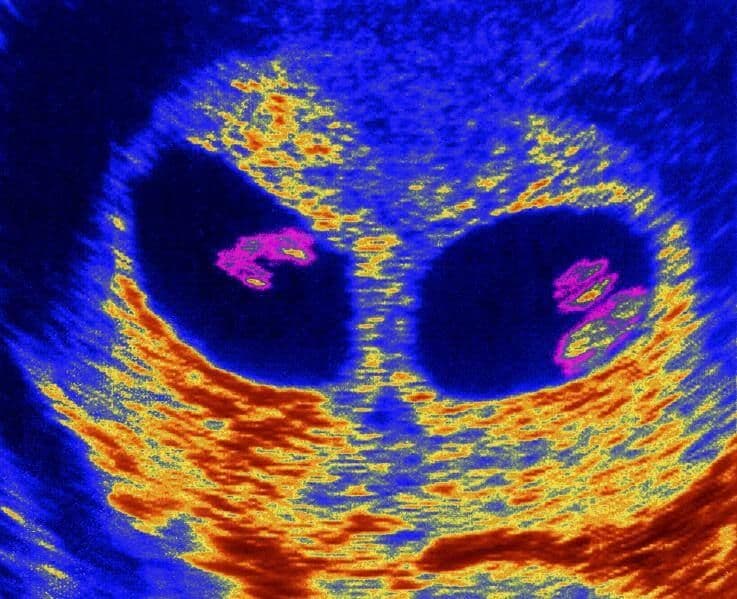

Whether or not you suspect anything, the first ultrasound scan will show definitely if you are carrying more than one baby.

The news that you’re having two or more babies may not always be delivered with the greatest tact. For instance, the sonographer may look at the scan and say that “something needs checking”. This sounds worrying, of course, but remember, he or she is only being cautious before giving you the life-changing news. The sonographer may also be checking your twins for size, to rule out any major problems. Once this is done, however, there are likely to be hearty congratulations.